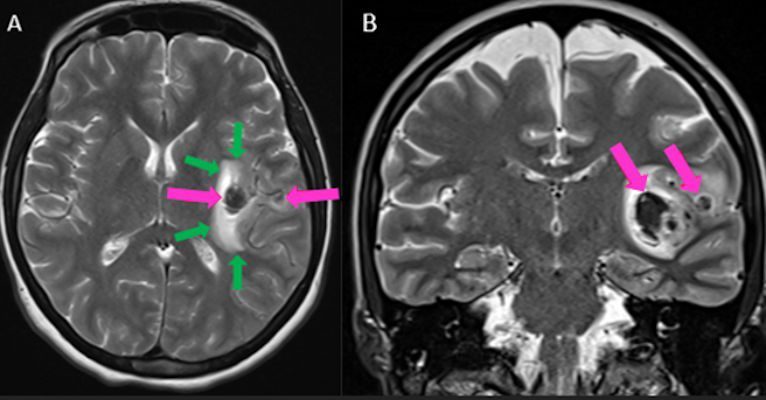

- Aksiyel (A) ve koronal (B) T2A görüntülerde sol insüler bölgede MCA M2 segmenti düzeyinde nodüler düşük sinyalli alanlar (oklar) ve vazojenik ödem ile uyumlu hiperintens alanlar (yeşil oklar) izleniyor.

- Kontrastlı T1A görüntüde (C) ve kontrastlı T1A çıkarma görüntüde (D) medialde bulunan alanda kontrastlanma izlenmezken (ok), lateralde bulunan boyutça daha küçük alanda kontrastlanma izleniyor (ok). Ayrıca anevrizma komşuğunda silvian fissürde leptomeningeal kontrastlanma görülüyor.